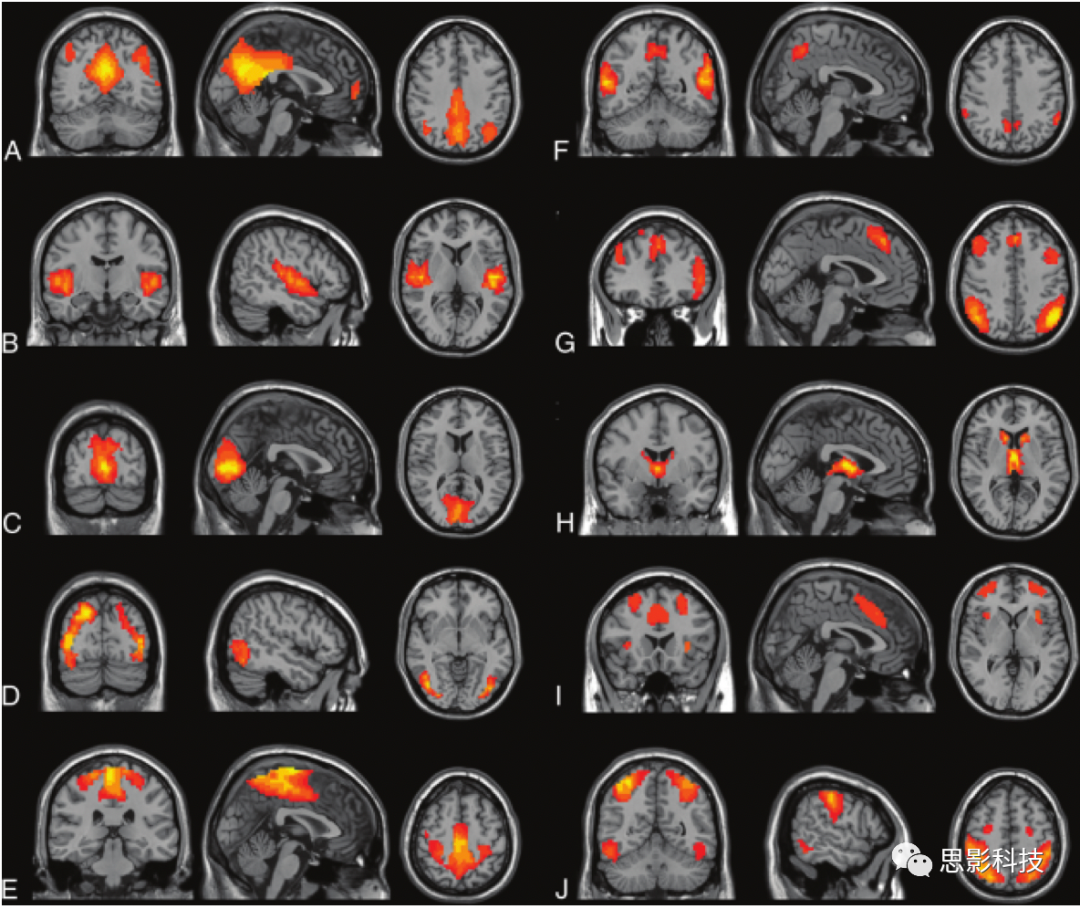

利用盲源分離的方法,分離出空間上相互獨(dú)立、時(shí)間序列相關(guān)的功能網(wǎng)絡(luò),通常分離出的幾種靜息態(tài)腦網(wǎng)絡(luò)包括但不限于:默認(rèn)網(wǎng)絡(luò),聽覺網(wǎng)絡(luò),突顯網(wǎng)絡(luò),執(zhí)行控制網(wǎng)絡(luò),視覺網(wǎng)絡(luò),感覺運(yùn)動(dòng)網(wǎng)絡(luò),背側(cè)視覺網(wǎng)絡(luò)(額頂注意網(wǎng)絡(luò))等。

200例健康志愿者ICA分析結(jié)果。

A,默認(rèn)網(wǎng)絡(luò) B,聽覺網(wǎng)絡(luò) C,內(nèi)側(cè)視覺網(wǎng)絡(luò) D,外側(cè)視覺網(wǎng)絡(luò) E,感覺運(yùn)動(dòng)網(wǎng)絡(luò) F,楔前葉網(wǎng)絡(luò) G,背側(cè)視覺網(wǎng)絡(luò)(額頂注意網(wǎng)絡(luò)) H,基底神經(jīng)節(jié)網(wǎng)絡(luò) I,執(zhí)行控制網(wǎng)絡(luò) J,視覺空間網(wǎng)絡(luò)